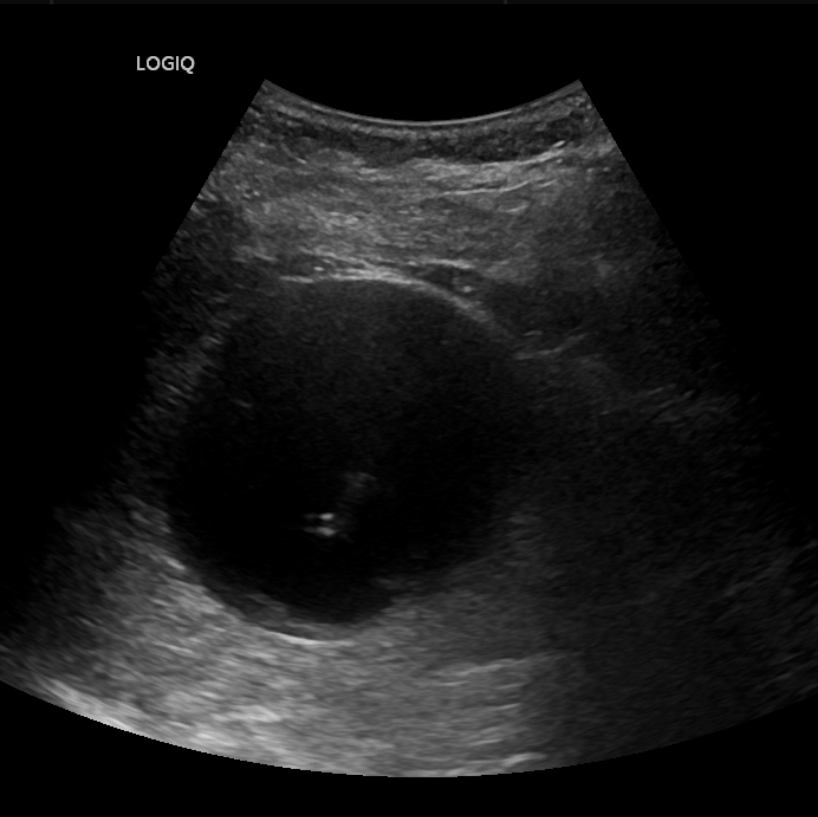

14岁女生小黄因小腹不适由母亲带至昆山市中医医院妇科就诊,超声检查后发现右附件区有一个8.0*7.2cm的巨大囊肿。由于正值初三备考的关键时期,如何解决囊肿还不能耽误复习迎考,这成了选择手术方式的关键点。

图片

▲小黄的影像学检查

超声介入团队联合妇科对患者进行全面综合评估后,认为超声引导下抽液硬化治疗是其最佳选择。待一系列术前常规检查后,在局部浸润麻醉下进行囊肿穿刺抽液硬化治疗。

整个治疗过程顺利,患者无明显不适,未影响其正常复习迎考。三月后腹部超声检查,右附件区囊肿已完全吸收。